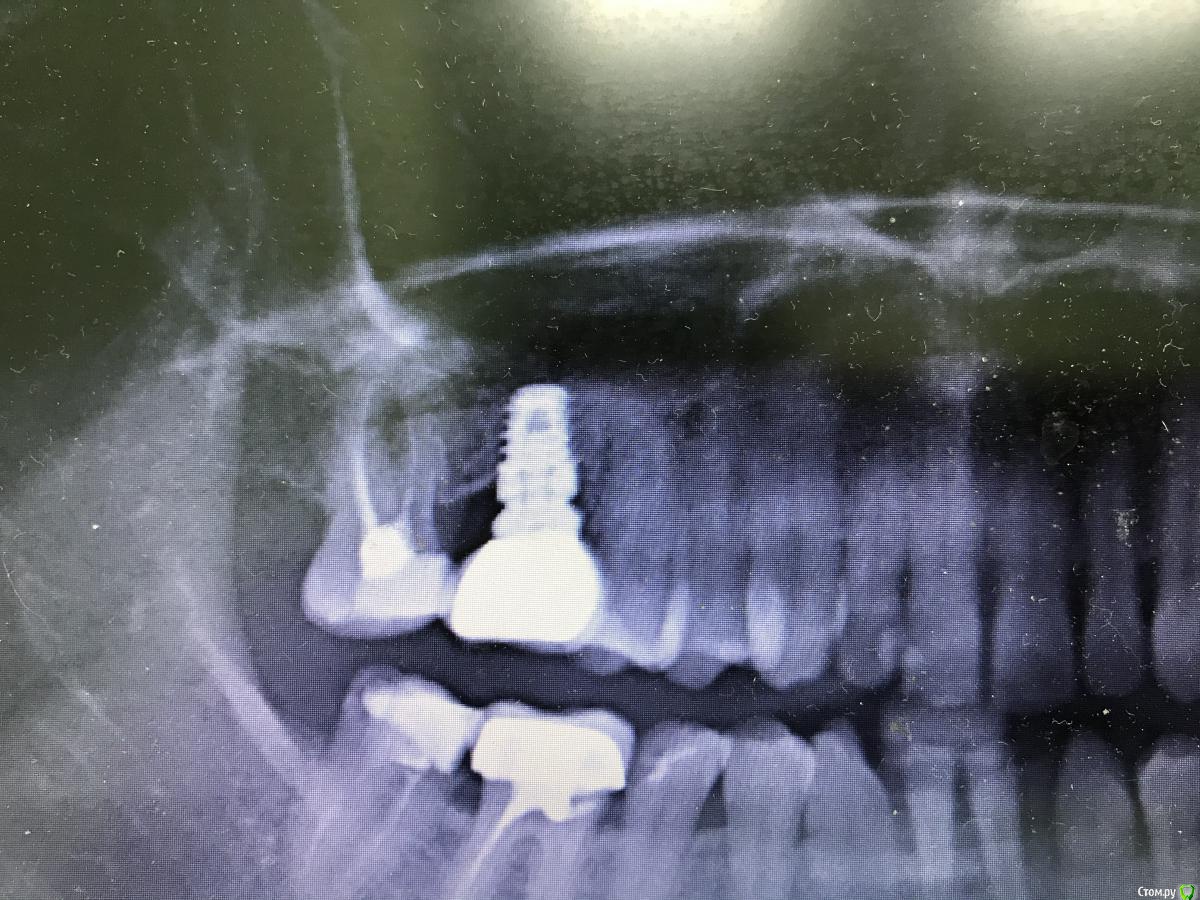

Жадный доктор Опубликовано 21 августа, 2020 Поделиться Опубликовано 21 августа, 2020 (изменено) Коронка сдана 4.5 года назад Изменено 21 августа, 2020 пользователем Жадный доктор Ссылка на комментарий

Fin Опубликовано 29 августа, 2020 Поделиться Опубликовано 29 августа, 2020 Коронка сдана 4.5 года назадЕсли нагрузку держит и не беспокоит я бы оставил Ссылка на комментарий